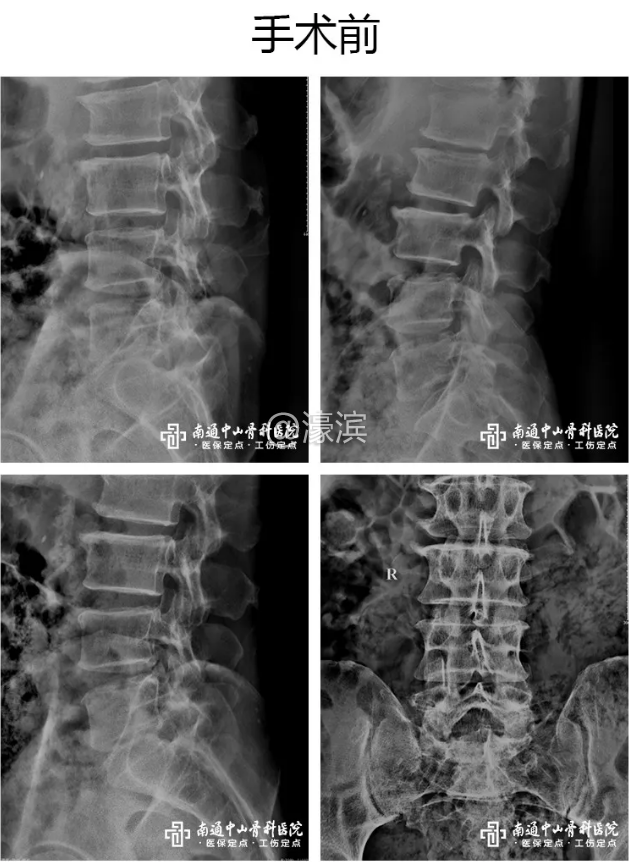

入院后,医务人员为金先生进行了全面仔细的检查,确诊为腰椎间盘突出症,手术指征明确。针对金先生的病情,胡玉华院长、丁荣清主任等进行会诊,确定采用“腰4、5、骶1全椎板切除减压+腰4/5椎间盘摘除+植骨融合钉棒内固定术”。

I/ O2 _! _% R& O1 k/ o  F9 y. Z8 {  术前,胡玉华院长将病情如实告知了金先生,且用深入浅出、通俗易懂的方式讲解了治疗方法,得到了患者和家属的一致认同。手术过程中,胡玉华院长、丁荣清主任凭借丰富的经验、细致的操作和精湛的技术,确保了手术的顺利完成。& ]' b4 n& G( t2 O3 h8 f